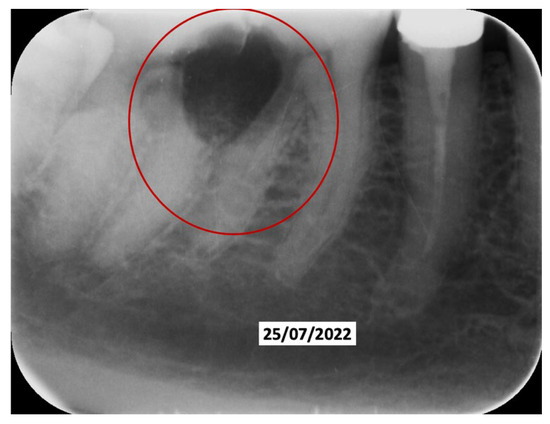

Just two weeks later, a rapid worsening was observed (documented with periapical intraoral X-rays) of the elements (13-12-23), which led to their necessary extraction (May 2022), with decontamination of the alveoli, with the beginning of a reabsorption process involving 14-15-16-46-47 (March 2022) with delivery of a removable partial prosthesis (Figure 5).

60 days after the extraction of the upper front teeth, it was discovered that the upper right premolars were also affected by significant root resorption, as well as 46 and 47 (Figure 6).

Figure 6. Evolution of the external resorptions in 46-47.